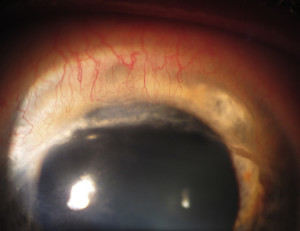

- Neovacularización corneal superficial periférica

Posteriormente se va produciendo un adelgazamiento estromal progresivo que avanza de forma circunferencial dando lugar a un surco periférico paralelo al limbo. Conforme la enfermedad avanza aparece una fina neovascularización corneal periférica desde el limbo que cruza este surco, y que produce depósitos lipídicos en el margen anterior del surco, que suele presentar un escalón pronunciado, a diferencia del borde posterior que suele presentar un perfil más suave de transición hacia el limbo.

El adelgazamiento corneal periférico, principalmente en las zonas superior e inferior, da lugar a un aplanamiento progresivo del meridiano vertical, lo que produce a la aparición de un astigmatismo contra la regla, que puede ser irregular, con la consecuente disminución de la agudeza visual, que suele ser el principal motivo de consulta de los pacientes con DMT. Otros pacientes pueden acudir por molestias, irritación, enrojecimiento o dolor en las formas inflamatorias de la enfermdad. En casos de adelgazamiento extremo se puede producir la perforación corneal, tanto de forma espontánea como secundaria a traumatismo(2).